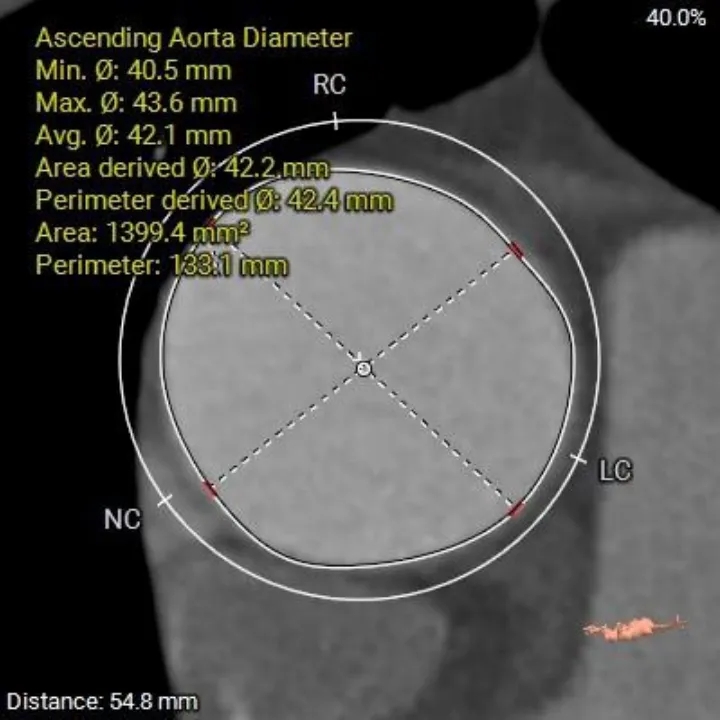

AAO

42.4mm

升主扩张